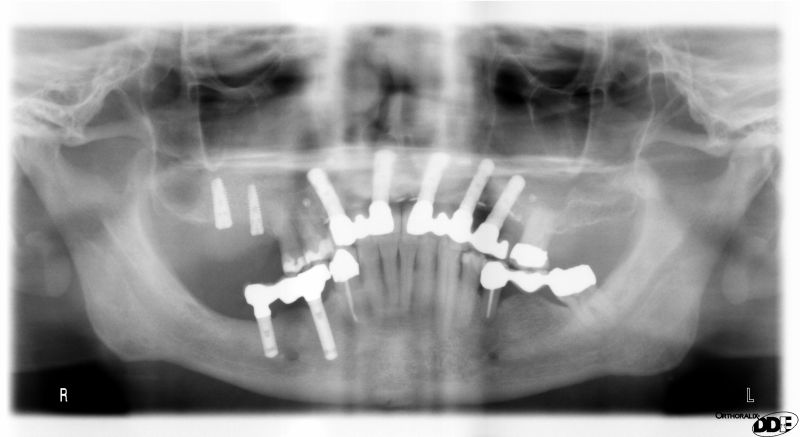

OPG of the initial situation – provision of missing denture in regio 44 to 47 by a resin-retained bridge